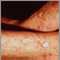

Actinic keratosis is a precancerous growth on the skin.

Actinic keratosis is caused by sun exposure. It occurs most commonly in fair skin, especially in the elderly and in young people who have light skin.

The skin lesion may be easier to feel than to see.